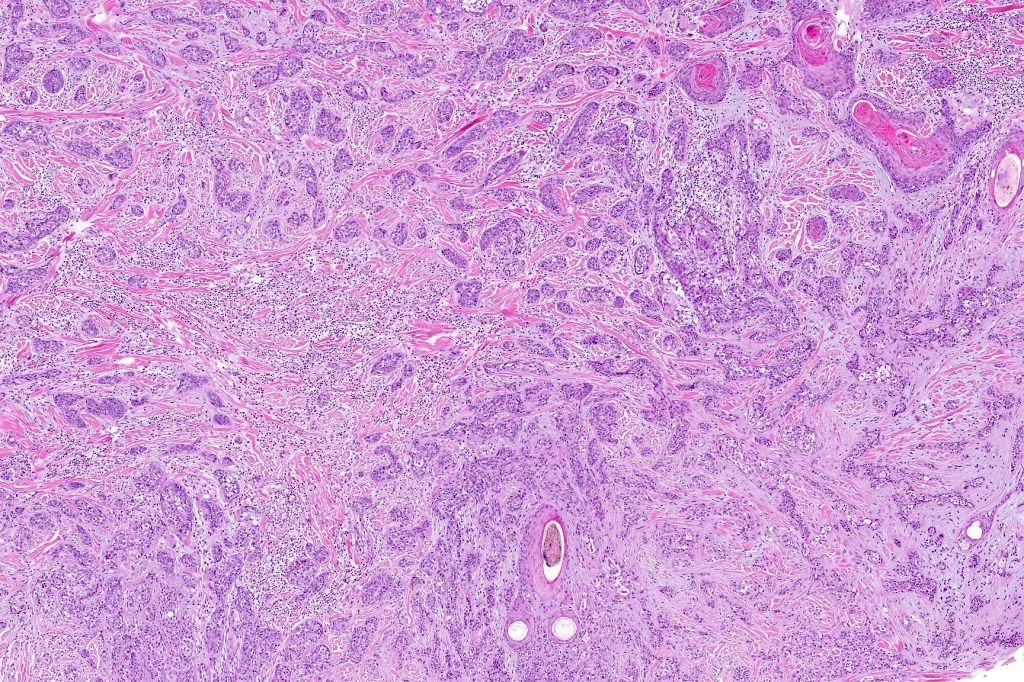

•Widely infiltrating biphasic tumor

•Adenocarcinoma in deeper reaches

•Variable pleomorphism and mitotic activity

•Often extends to the subcutaneous fat

•Perineural infiltration is commonly seen